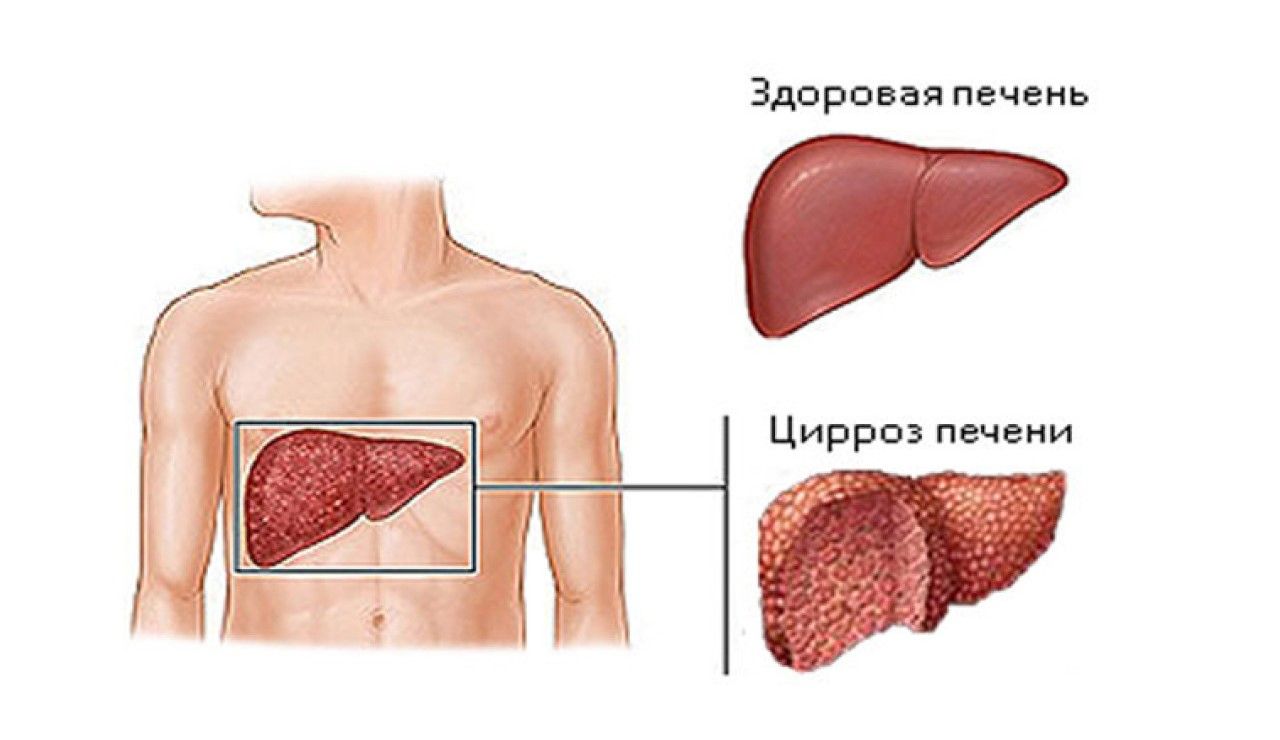

Признаки заболеваний печени: Важные симптомы и рекомендации